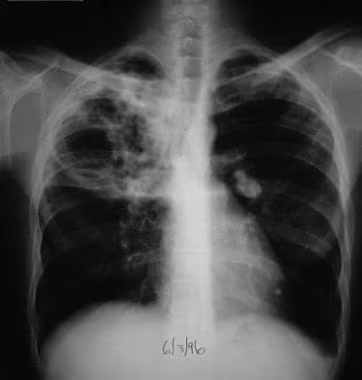

પલ્મોનરી ટ્યુબરક્યુલોસિસ એ સીરિયસ ઇન્ફેક્શન છે જે બેક્ટેરિયમ માયકોબેક્ટેરિયમ ટ્યુબરક્યુલોસિસ નામના બેક્ટેરિયા ને કારણે થાય છે જે મુખ્યત્વે લંગ્સ ને અફેક્ટ કરે છે પરંતુ તે બોડીના બીજા એરિયામાં પણ સ્પ્રેડ થાય છે.

પલ્મોનરી ટ્યુબરક્યુલોસિસ એ એર થ્રુ સ્પ્રેડ થાય છે એટલે કે ઇનફેક્ટેડ પર્સનના કફિંગ કે સ્નીઝિંગના કોન્ટેકમાં આવવાથી સ્પ્રેડ થાય છે.

Explain the diagnostic evaluation of pulmonary tuberculosis (પલ્મોનરી ટ્યુબરક્યુલોસિસ ના ડાયગ્નોસ્ટિક ઇવાલ્યુએશન જણાવો).